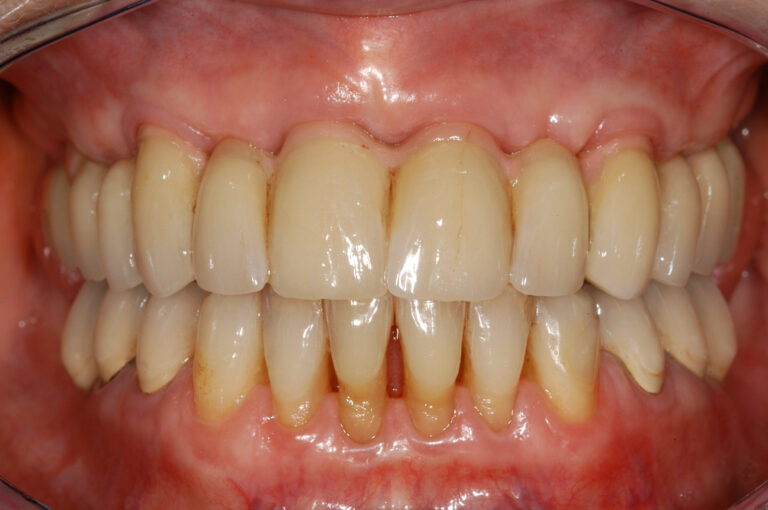

Following improvements to the surfaces of our implants, and utilising experience gained over many years, we can now offer you “FIXED TEETH TODAY”. In most cases, we are able to place a fixed bridge onto the implants immediately after placement. You would therefore arrive at the surgery with loose dentures, and leave with a number of implants placed and a FIXED bridge fitted onto them. This concept reduces the discomfort and healing time following implant placement, and provides immediate satisfaction to our patients. Imagine being able to bite into an apple again for the first time in many years!

The most common cause of partial tooth loss is failing crowns or bridges. The natural roots are then too weak to support a bridge, and have to be extracted. We would usually extract the failing roots, place implants directly into their sockets, and place a fixed bridge immediately afterwards.